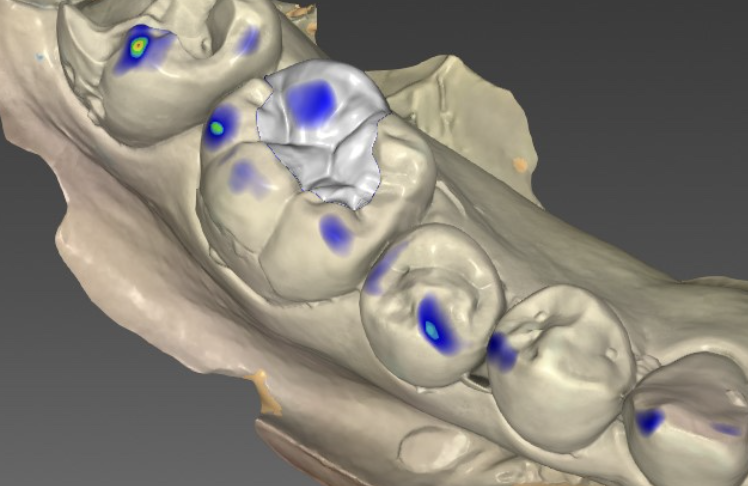

歯の形状デザイン